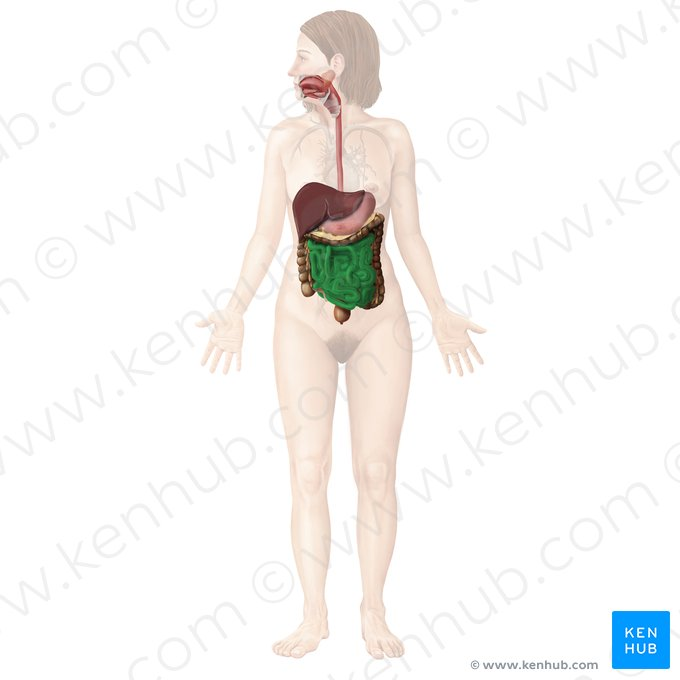

Liver

a large organ located in the upper right abdomen that produces bile, detoxifies blood, and performs many other metabolic functions.

Considered as the largest gland in the body

Small intestine / colon

the part of the digestive tract located between the stomach and the large intestine, where most of the digestion and absorption of nutrients occurs.

Large intestine / colon

the final section of the digestive tract, responsible for absorbing water and electrolytes and forming feces.